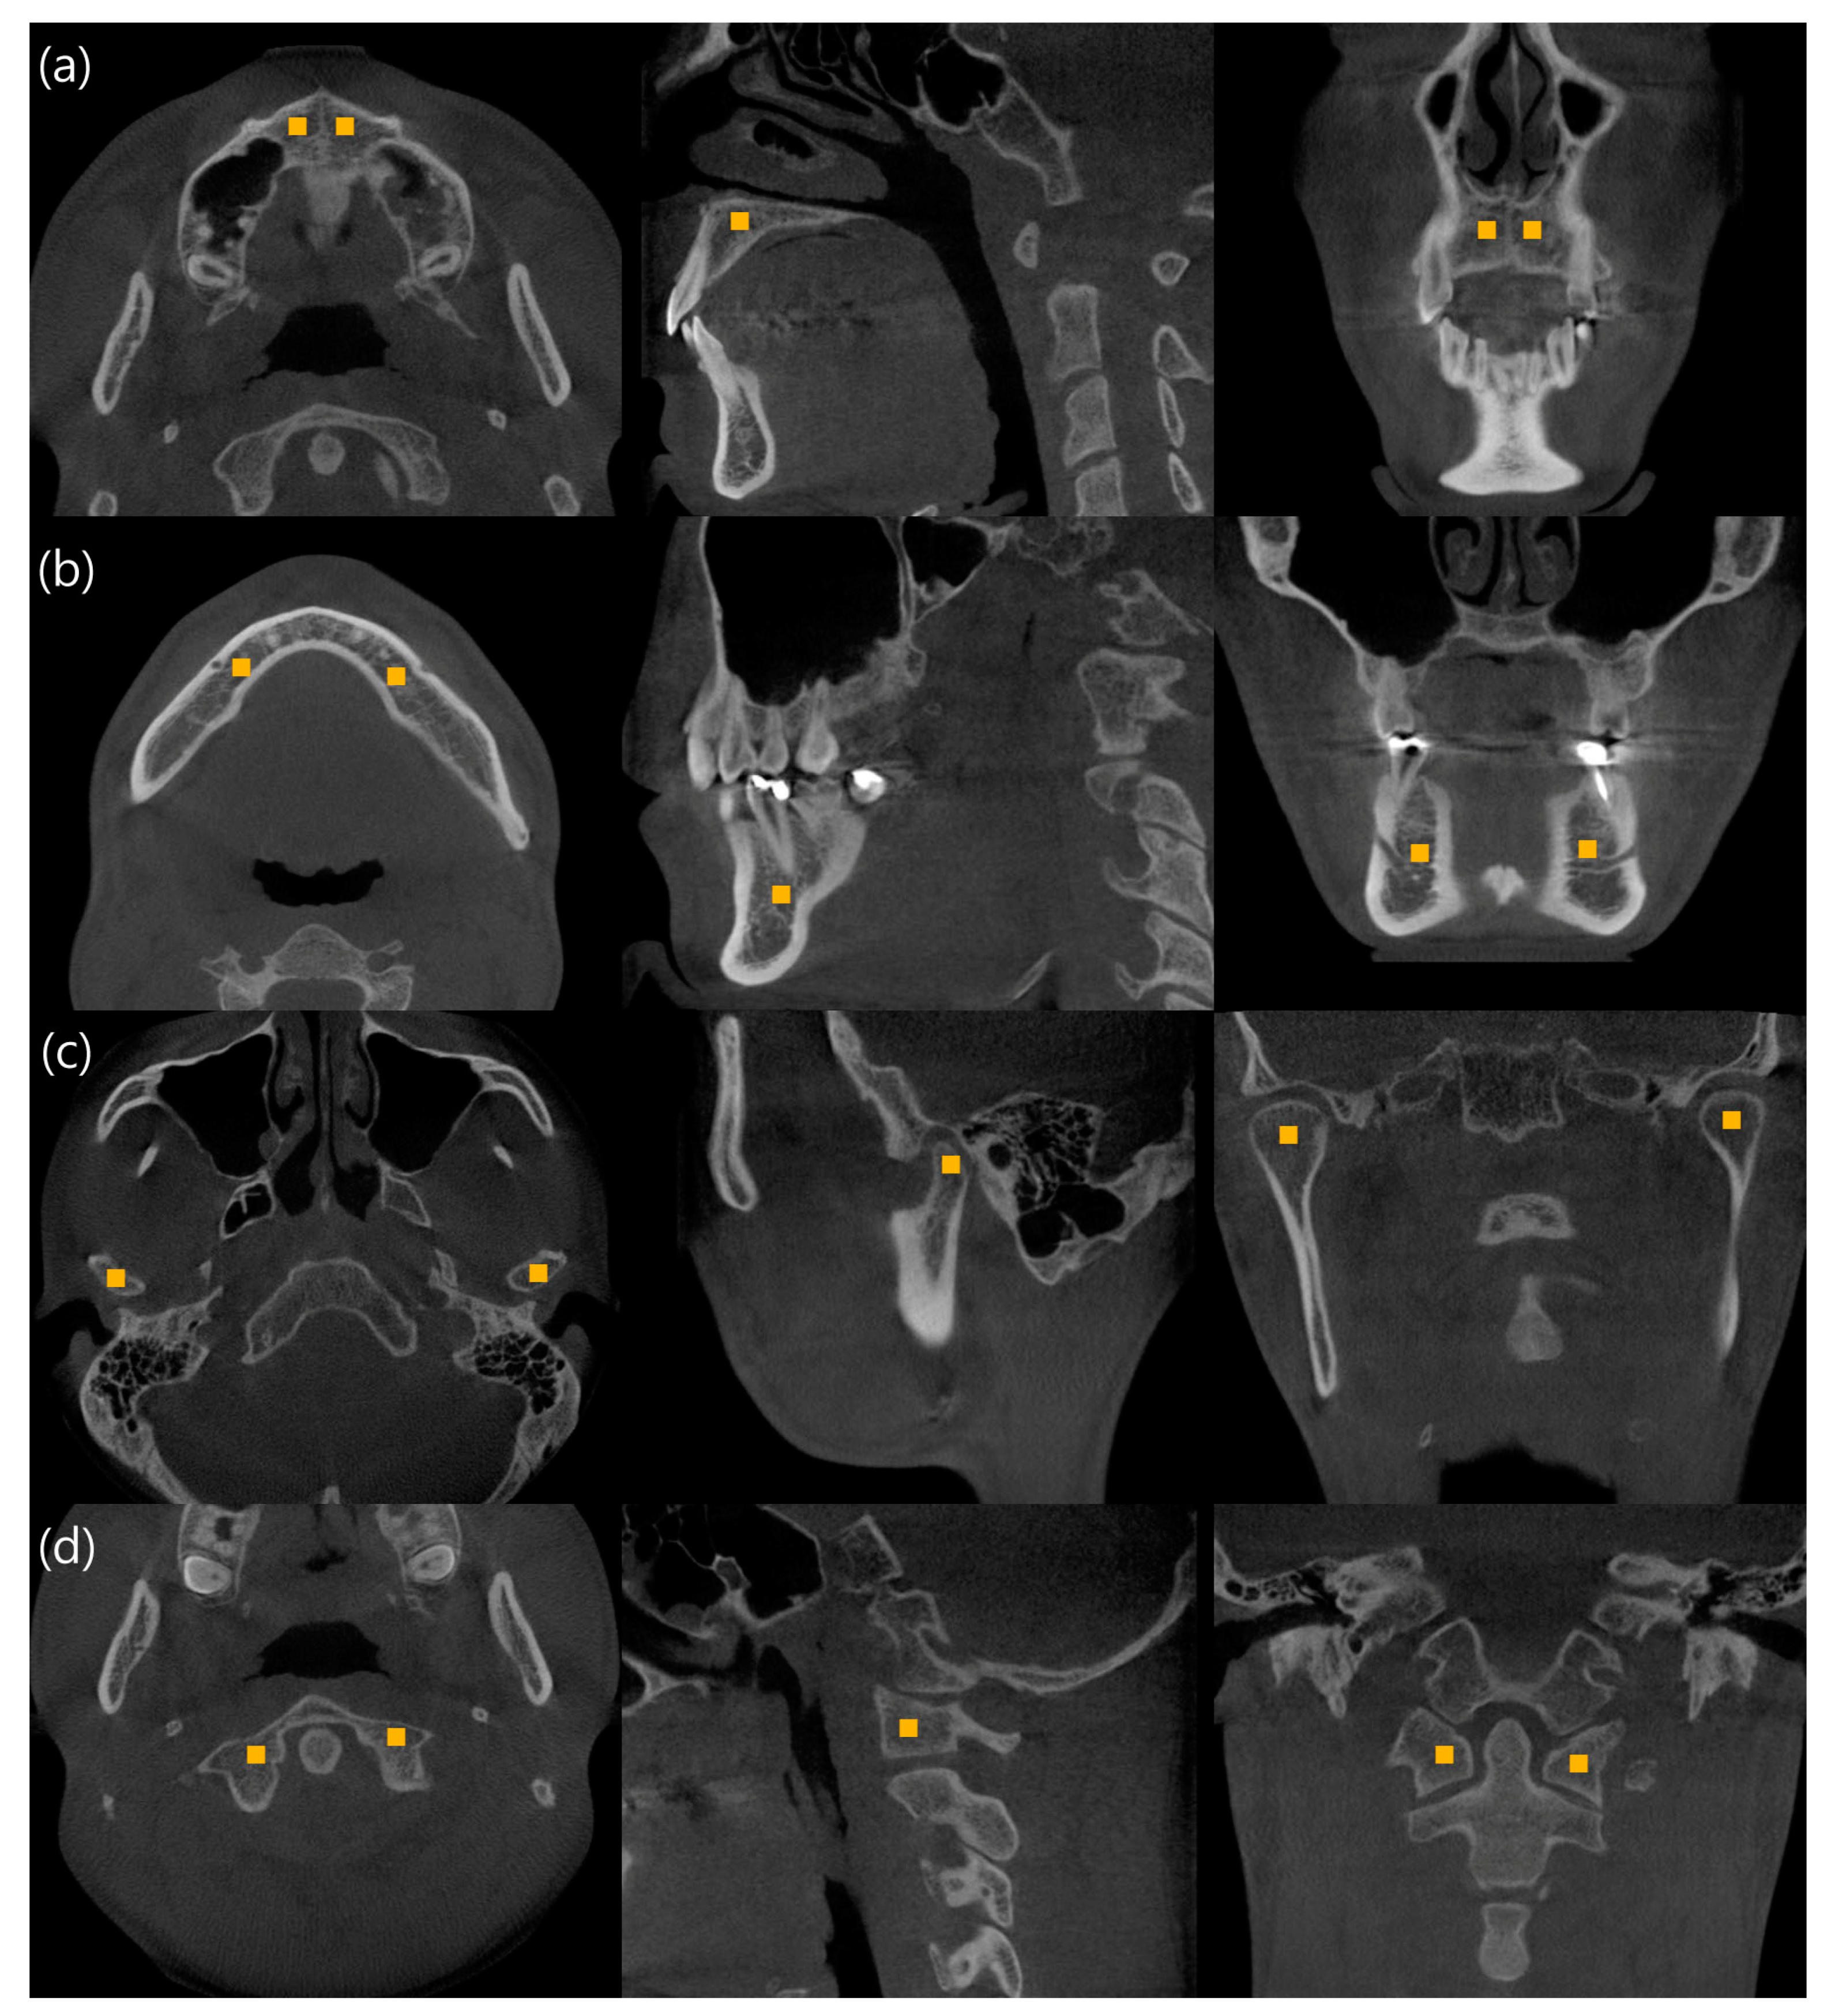

2. Materials and Methods